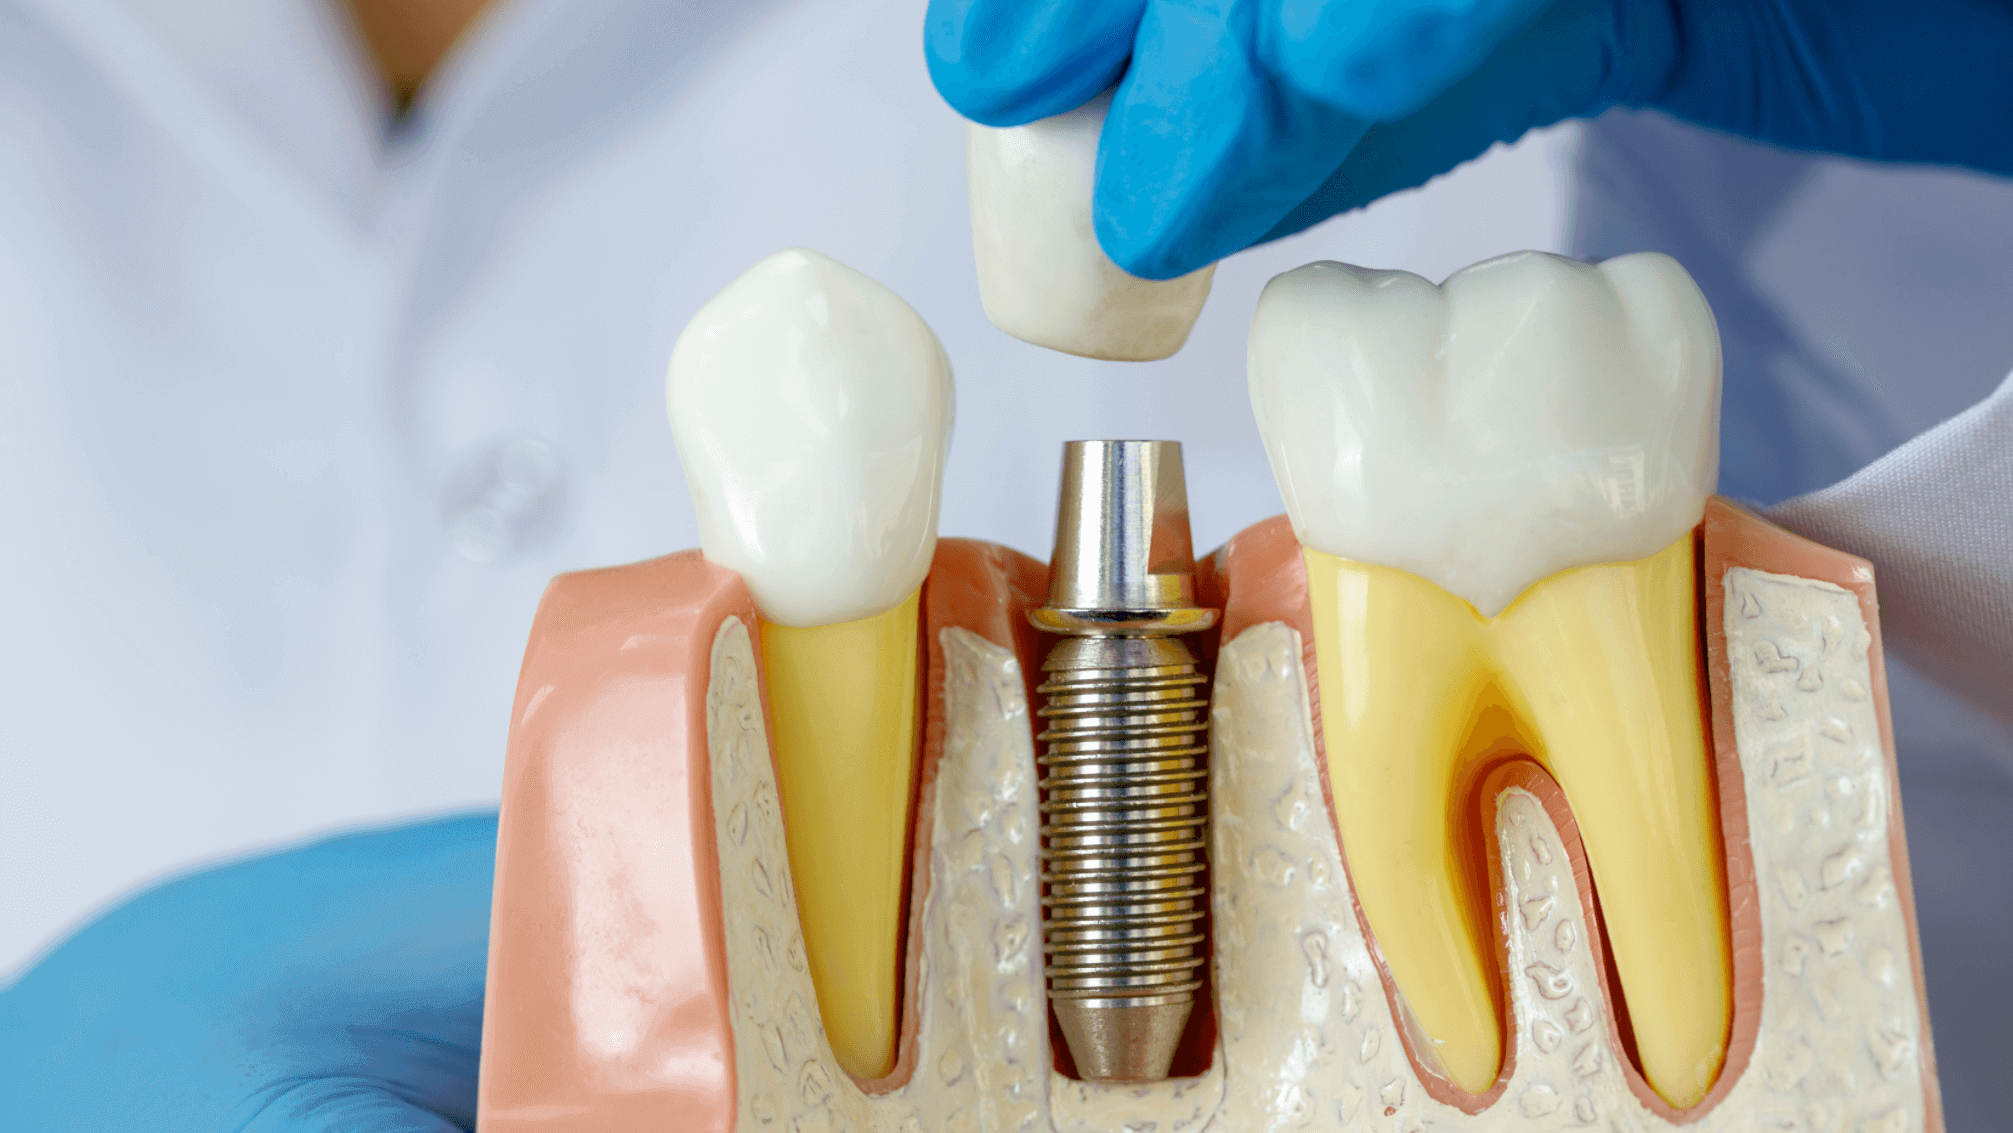

Advanced Implant Surgery

What Can Be Done If There Is Not Enough Bone For Implant Procedure?

What is Advanced Implant Surgery?